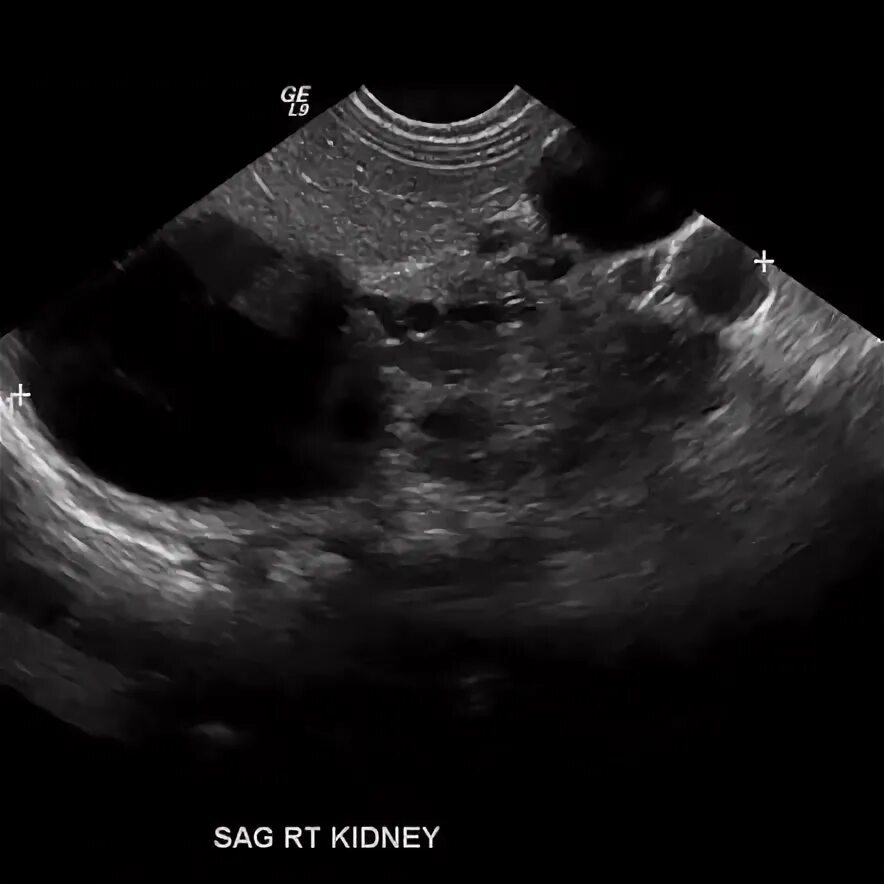

Мультикистозная почек плода